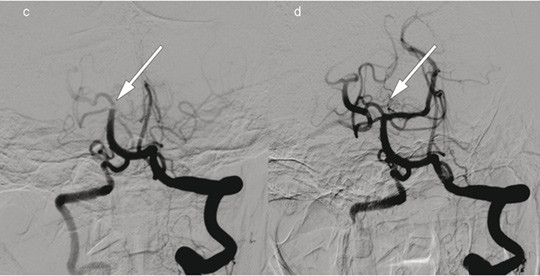

Patient 1. A man in his 70s was admitted with acute right-sided paralysis. The neurological outcome was scored on the National Institutes of Health Stroke Scale (NIHSS) to 21 points (severe cerebral infarction), and intravenous thrombolytic therapy was administered. The image to the left shows cerebral angiography with contrast injection in the left internal carotid artery, a) before and b) after embolectomy of a so-called T-occlusion (arrows) in the left carotid siphon and middle cerebral artery. The thrombus was removed and blood flow to the left hemisphere was restored 195 minutes after symptom onset. Further workup revealed atrial fibrillation and an embolic cerebral infarction in the middle cerebral artery territory. The patient received anticoagulation therapy with rivaroxaban. The NIHSS score was 0 points at follow-up three months later.